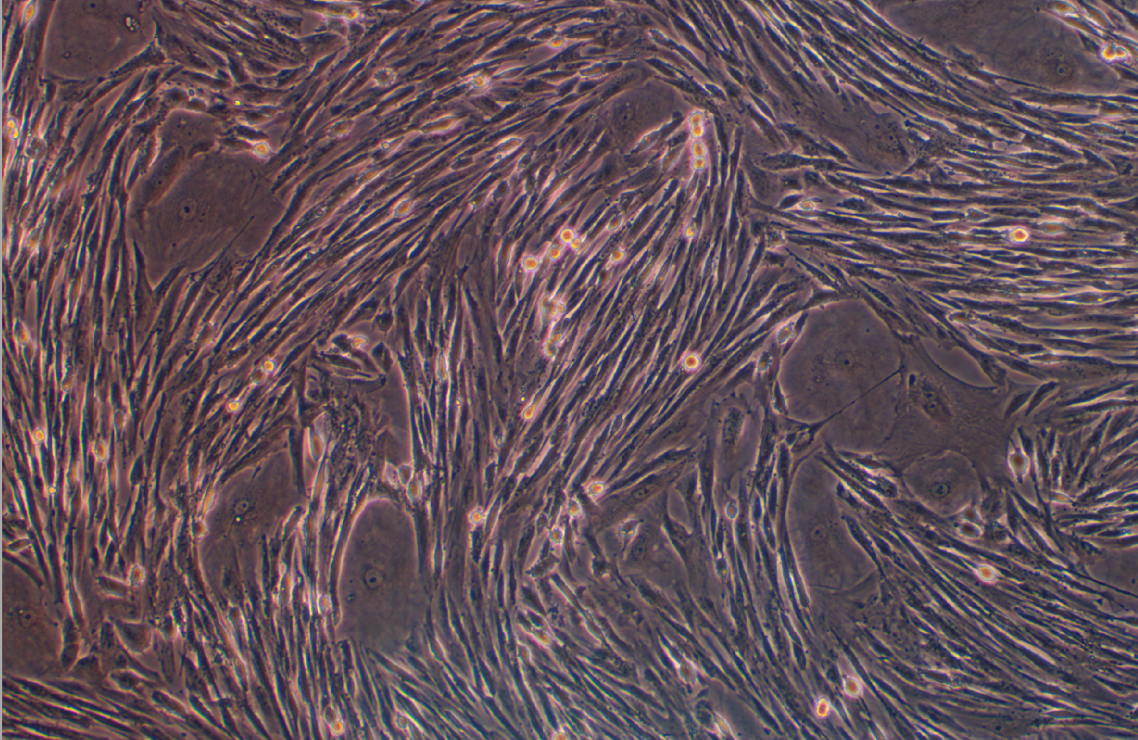

形態 |

長梭形細胞樣 |

生長特征 |

貼壁生長 |

成纖維細胞是肺間質中含量最豐富的細胞種類。這些成纖維細胞與普通的相似 ,但也有其特有的特征 ,例如具有很長 的偽足和細胞間的間隙連接,肺成纖維細胞的主要功能為分泌肺泡隔基質中的III型膠原 ,彈性蛋白以及蛋白多糖 ,也在 肺部受損時擔任重要的修復和重建功能。肺部受傷后 ,在炎癥部位的一定程度的成纖維細胞積聚是肺部復原的關鍵步 驟 ,過多或者不足的成纖維細胞聚集都會導致肺功能異常。 |